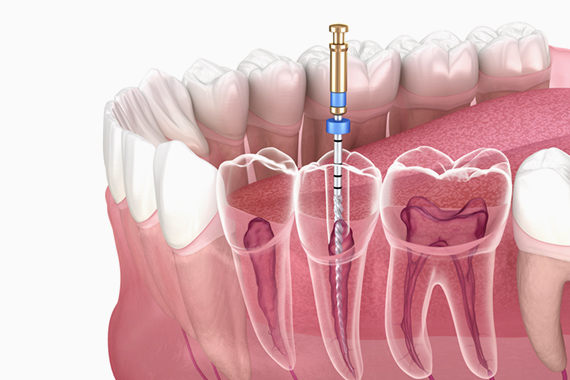

根管治療について

進行してしまったむし歯に対して

根管治療で歯を残す選択ができます

歯の根を治療することであり、むし歯が進行して歯の内部や根元まで感染が進んでいる場合に根管治療を行います。歯の内部や根元は細かく複雑な構造をしているため、精度の高い治療が必要です。当院では根管治療に対応しており、各種設備を活用して質の高い治療をご提供いたします。

Nitiファイル

根管内の感染部分を取り除くため、柔軟性に優れたニッケルチタン(NiTi)ファイルを使い、細部まで丁寧に治療を行います。

根管拡大装置(トライオート)

治療を迅速かつ安全に実施できる高性能モーターです。電動制御のため、感染部分をより正確に除去し、患部の無菌状態を作り上げます。